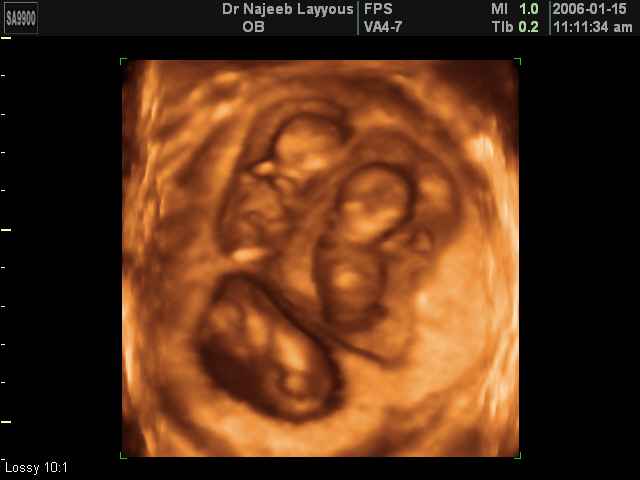

- صور لتوائم

صور لتوائم بجهاز الالتراساوند ثلاثي الأبعاد | الدكتور نجيب ليوس